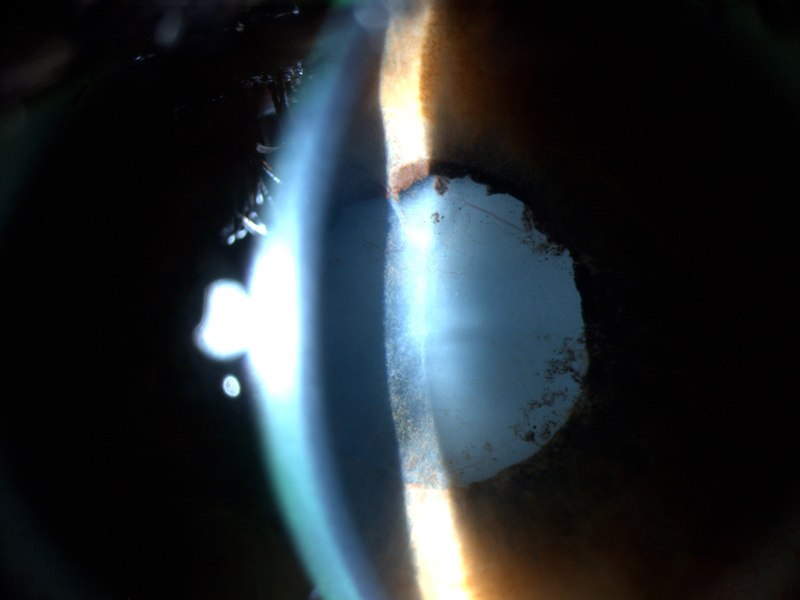

Figura 3).

Figura 3. Catarata secundaria a uveítis asociada a AIJ. Se observan neovasos en cápsula anterior del cristalino.